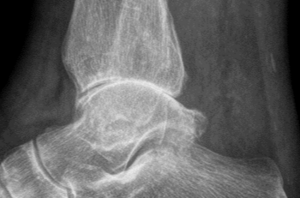

Sprunggelenksarthrose

Das obere Sprunggelenk (OSG) muss von allen Gelenken die größte Belastung tragen und ist daher auch besonders anfällig für Verschleißerscheinungen wie Arthrose. Prof. Dr. med. Dr. phil Victor Valderrabano ist ein international renommierter Spezialist für Orthopädische Chirurgie und Chefarzt des SWISS ORTHO CENTER in Basel, Schweiz. Er beantwortet die wichtigsten Fragen rund um die OSG-Arthrose und ihre Behandlungsmöglichkeiten.

Prof. Valderrabano: „Eine Arthrose im Sprunggelenk ist sehr viel schmerzhafter als eine Arthrose im Knie- oder Hüftgelenk. Die Betroffenen leiden häufig dauerhaft unter Schmerzen, sowohl tagsüber in Bewegung und Belastung, als auch nachts in Ruhestellung. Anders als bei einer Knie- oder Hüftgelenksarthrose ist die Verschleißerscheinung im Sprunggelenk keine altersbedingte Erkrankung. Die Ursachen liegen in 80 Prozent der Fälle in einer vorausgegangenen Verletzung wie z.B. einem Bruch bei einem Unfall, Umknicktrauma mit Bandinstabilität oder einer Schwäche der Sehnen und Muskel. Eine Fehlstellung, wie z.B. ein Knick-Senkfuß oder Hohlfuss, kann ebenfalls eine Arthrose hervorrufen. Profisportler, z.B. im Fußball oder Tennis, sind durch die extreme Belastung auch dafür prädestiniert, eine OSG-Arthrose zu entwickeln.“